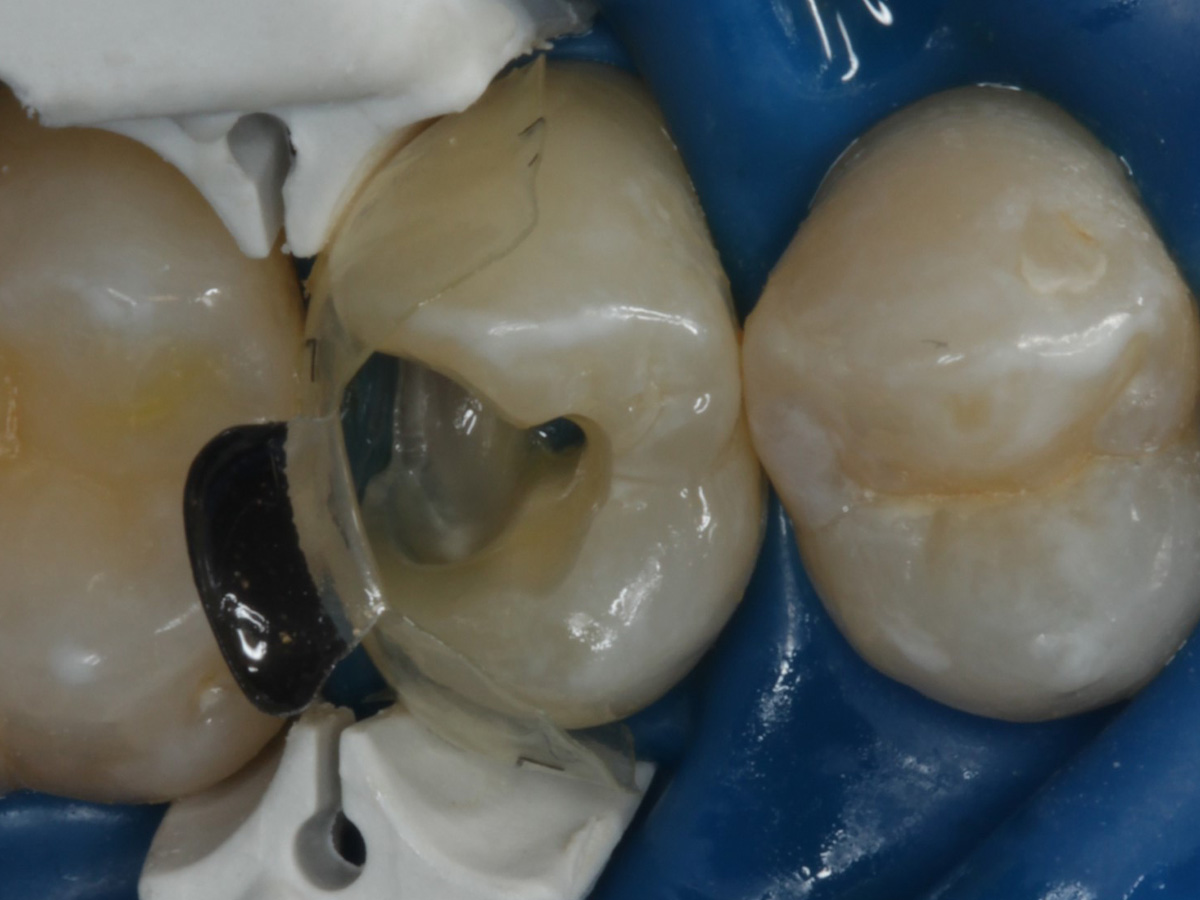

Abbildung 24

Folgesitzung: Trepanation Zahn 25

Abbildung 25

Nadelaufnahme nach elektronischer Längenmessung